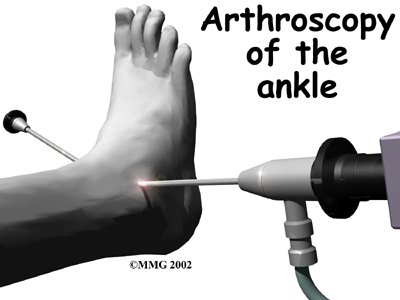

Arthroscopic Debridement

Sometimes when OA of the ankle occurs, loose pieces of cartilage and bone float around inside the ankle joint. These loose bodies can cause irritation in the joint, leading to inflammation. They can also get caught between the joint surfaces of the ankle. This can cause a sharp pain when it happens. The cartilage surfaces of the joint also become rough, with flaps of cartilage that peel off the surface, much like paint peeling off the ceiling. Bone spurs, or outgrowths, form around the joint and can grow larger over time. These bone spurs can rub against the soft tissues around the ankle joint when the ankle moves, again causing pain and swelling.

The arthroscope can help the doctor remove these loose bodies and bone spurs and smooth the cartilage surfaces of the ankle joint. The arthroscope is a special TV camera that is inserted through small incisions (one-quarter of an inch) around the ankle. Small surgical tools can also be inserted through these incisions to work in the ankle joint.

The arthroscope can help the doctor remove these loose bodies and bone spurs and smooth the cartilage surfaces of the ankle joint. The arthroscope is a special TV camera that is inserted through small incisions (one-quarter of an inch) around the ankle. Small surgical tools can also be inserted through these incisions to work in the ankle joint.